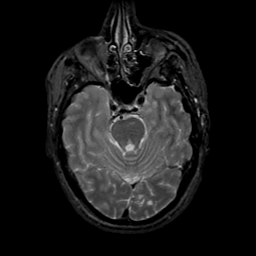

MR Study #18, July 21, 1991 -- Slice #16